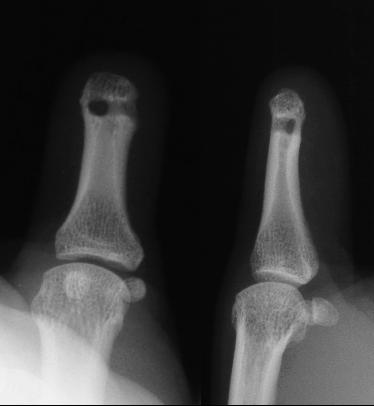

The thumb preop: hook nail deformity:

Bone tip just beneath the skin, line on the film traces the thumbnail edge.